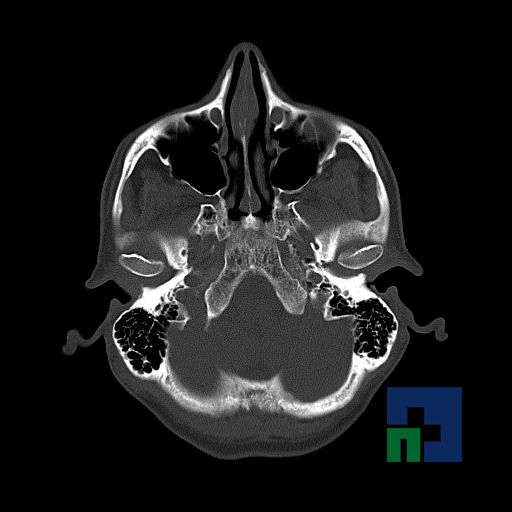

- Diagnosticul traumatismelor de bază de craniu

- Diagnosticul fracturilor:

- Complexe cranio-sinusale

- Complexe cranio-etmoidale

- Complexe cranio-orbitare

- Complexe cranio-faciale